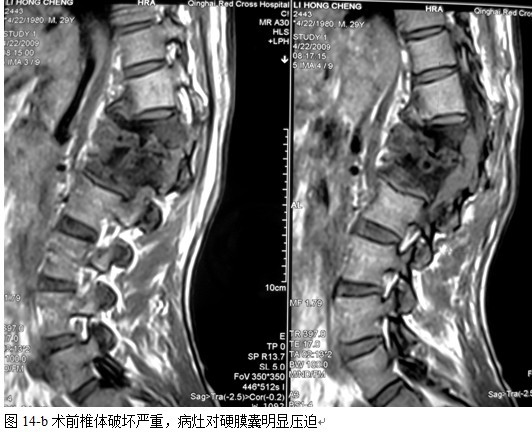

2.2 手术方法

全麻后气管插管,俯卧位,根据术前影像学分析确定需显露的椎体数目。

图11-a术前

以病变椎体为中心,作一后正中切口,显露病椎棘突、椎板、关节突以及上下需要固定的正常椎体,根据后凸畸形的严重程度在C 型臂协助下确定进钉角度和方向,置入椎弓根钉,椎弓根钉固定的方法:病灶上下相邻正常椎体置入,当病椎骨质破坏不超过1/3或未累计椎弓根时置入相对较短的钉子,一般长度为35mm,当骶1椎体有破坏时,根据骨质的情况确定入钉的方向,将病椎上、下关节突关节切除,自椎间孔显露病灶,直视神经根状态下进行病灶清除和椎管减压,可将干酪样物,死骨,坏死的椎间盘大部分清除,解除硬膜囊的压迫,必要者可双侧同时病灶清除,减压。无钛棒状态下用椎体撑开器轻柔牵开,采用前路撑开结合后路固定维持有限撑开或加压缓慢矫正脊柱后凸畸形,特别注意是由于结核患者骨质疏松,不可用钉棒大力撑开,否则钉子拔出可能性较大。要前路撑开加后路加压来达到矫形的目的。撑开后,缺损空间增大,大部分用手指可触及缺损内的情况,能进一步彻底清除病灶及对侧的病灶,反复用异烟肼盐水混合液冲洗病灶,凿出植骨床,植骨时需注意植骨块要采用“平进竖植”方法,循序用植骨打入器和辅助器械缓慢植入否则易导致神经根损害。植骨完成后再次采用内固定适当加压促使骨块稳定及融合,如果病灶中的脓液稀薄较多时,在病灶中留置一根硬膜外管,术后注射异烟肼,每周两次,以提高局部的药物浓度,在对侧椎板,关节突间植骨,病灶内留置链霉素2.0g ,放置引流管,闭合伤口。

脊柱结核手术治疗的传统术式是病灶清除椎管减压术。其目的是清除病灶及椎管内脓汁、干酪样坏死物、死骨,保障抗痨药物的渗透,促进病灶愈合,解除脊髓压迫。不足之处在于死骨不能完全清除的可能,残留椎间盘不能完全清除的可能。凿开病灶清理后椎体间残留空间大,前中柱结构的破坏和缺失,造成脊柱不稳,后凸畸形加重的可能,造成迟发型神经损伤的可能且植骨块在压力状态下再度脱落吸收的可能性较大。在结核病灶内使用内置物的安全性已经得到实验及临床研究的证实[9、11],内固定的应用使脊柱结核的手术治疗取得了很大进步,但在手术方式的选择上,选择前路病灶清除植骨内固定,还是一期后路经椎弓根内固定结合前路病灶清除植骨融合,目前仍有争议[12、13、14、15、16、17、18、19、20、21],选择前者的学者认为通过一个入路,一次完成所有手术操作,可以避免再行后路内固定的手术创伤,而且椎间植骨的融合率较后外侧融合率高,但前路暴露创伤大,内固定的植入存在一定的风险和困难,前路内固定主要重建脊柱的前中柱,前路内固定适于1-2椎体的的破坏,对于多个椎体的结核前路的手术效果较后路差。选择后者的学者认为,后路固定可以避免在病灶内应用内固定,安全性更有保障,但需要两个切口,创伤大,术中需改变体位,而我们的方法取其两者的优点,只有后侧单一切口,创伤相对小,置入椎弓钉相对容易,而且后路椎弓根钉棒系统固定为三柱固定,作用强大,在清除病灶时,我们选择有脓肿,破坏严重,神经症状重的一侧,通过关节突关节,采用刮,凿,切,咬等方法逐步彻底清除病灶,用椎体撑开器逐步撑开椎间,这样更有利于后凸畸形的矫正。对于前方病灶对硬膜压迫较重的患者,只能先行前路病灶清除,撑开时不必担心前路病灶对的压迫病灶完全清除后,准备植骨床,前路植骨后,可对植骨块用椎弓根系统加压,使其更为稳定。另一侧椎板和关节突处可植入碎骨,融合率明显提高,对于脓肿我们首先充分引流,然后用长的刮勺刮除脓肿壁的脓胎,再用干纱布反复擦拭,只到有大量的出血点,再反复用异烟肼与盐水的混合液加压冲洗创面,可以降低局部的细菌量,最后经皮在病灶中放置硬膜外管,术后注射异烟肼,可以提高局部化疗药物的浓度,减轻毒副反应,对于降低病变的复发也有很大作用。